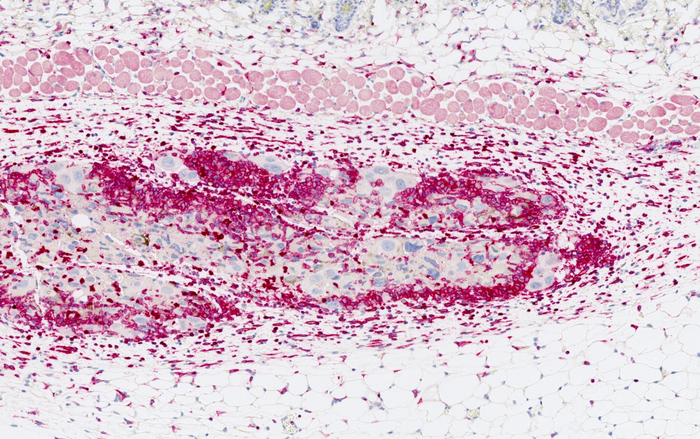

图片:免疫细胞浸润(深红色)在衰老的癌细胞(大细胞核用蓝色标记)周围。

由ICREA研究员Manuel Serrano博士和现任职于瑞典卡罗林斯卡研究所的Federico Pietrocola博士领导的巴塞罗那IRB的科学家们,已经研究了诱导癌细胞衰老如何在比死亡癌细胞更大程度上提高免疫反应的有效性。在用衰老的癌细胞给健康的老鼠接种疫苗,然后刺激肿瘤的形成后,研究人员观察到,这些动物没有患癌症,而且患癌症的数量显著减少。他们还分析了接种疫苗对已经发生肿瘤的动物的效果。在这种情况下,尽管由于肿瘤的保护屏障,结果较为温和,但也观察到改善。

研究人员在黑色素瘤的动物模型中测试了这项技术,黑色素瘤是一种以免疫系统高度激活为特征的癌症,在胰腺癌模型中也测试了这项技术,胰腺癌对免疫细胞产生了强大的屏障。衰老癌细胞的预防性接种治疗对这两种类型的肿瘤都有效。他们还用癌症患者的肿瘤样本作为研究的补充,并证实,当人类癌细胞之前被渲染为衰老时,它们也有更大的能力激活免疫系统。

在本研究中观察到,衰老细胞呈现独特的信号,这些信号通过免疫系统的激活和刺激识别,不同于诱导衰老前细胞所呈现的信号。